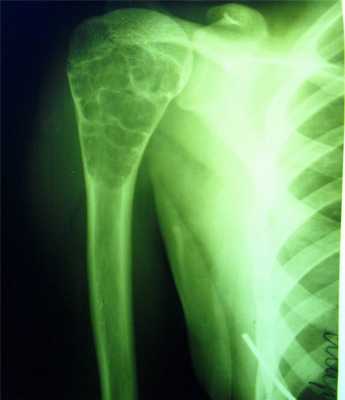

Все больные были разделены на группы в зависимости от размера очагового образования: 1-ю группу (диаметр ООЛ 0,5-1; рис. 1) составили 9 мужчин и 14 женщин, 2-ю группу (диаметр ООЛ 1-2 см; рис. 2) - 30 мужчин и 13 женщин, 3-ю группу (множественные ООЛ; рис. 3) - 27 мужчин и 17 женщин.

Рис. 1. Компьютерная томограмма груди пациента 1-й группы

Больные 1-й группыбыли оперированы из миниторакотомного доступа, 2-й - из миниторакотомного доступа с видеоподдержкой, 3-й - из видеоторакоскопического доступа. Результаты гистологического исследования удаленных патологических образований представлены в таблице.

Очевидно, что в настоящее время остается нерешенным вопрос о показаниях и противопоказаниях к оперативному удалению одиночных образований легких размером от 0,5 до 1 см, диагностические алгоритмы у подобных пациентов также сформулированы нечетко. По нашим данным, злокачественное поражение легких и плевры в этой группе было диагностировано у 3 (13%) пациентов, доброкачественные опухоли - у 5 (21,7%).